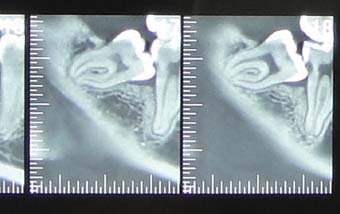

↑ちなみにこれが問題の歯。(CT画像)

根が変に曲がってている上に、変な方向を向いて生えています。